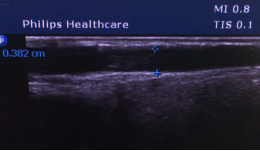

附图

(三) 手术前后血管对比示意图